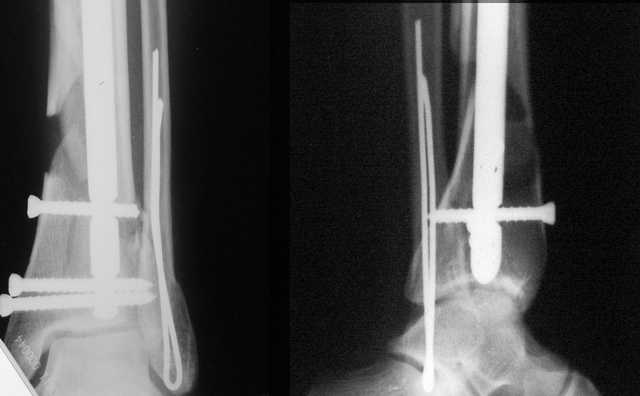

Аргументы: перелом достаточно низкий, трудно будет ввести 3-и блок. винта, а учитывая характер перелома на 2-х дистальных винтах я бы не рекомендовал немедленную полную нагрузку.

Положим, и с 2 винтами она к 2 месяцам была бы тут вполне реальна. Кроме того, есть возможность ввести винты мимо гвоздя (Poller), и таки разрешить раннюю полную нагрузку (что еще зависит от массы тела пациента и диаметра винтов). А уж если сопоставить стоимость отечественного гвоздика и пластины Synthes... Если бы на порядок более дорогая железка давала на тот же порядок лучший результат... ;-)

Кликните для загрузки файла 1.JPG